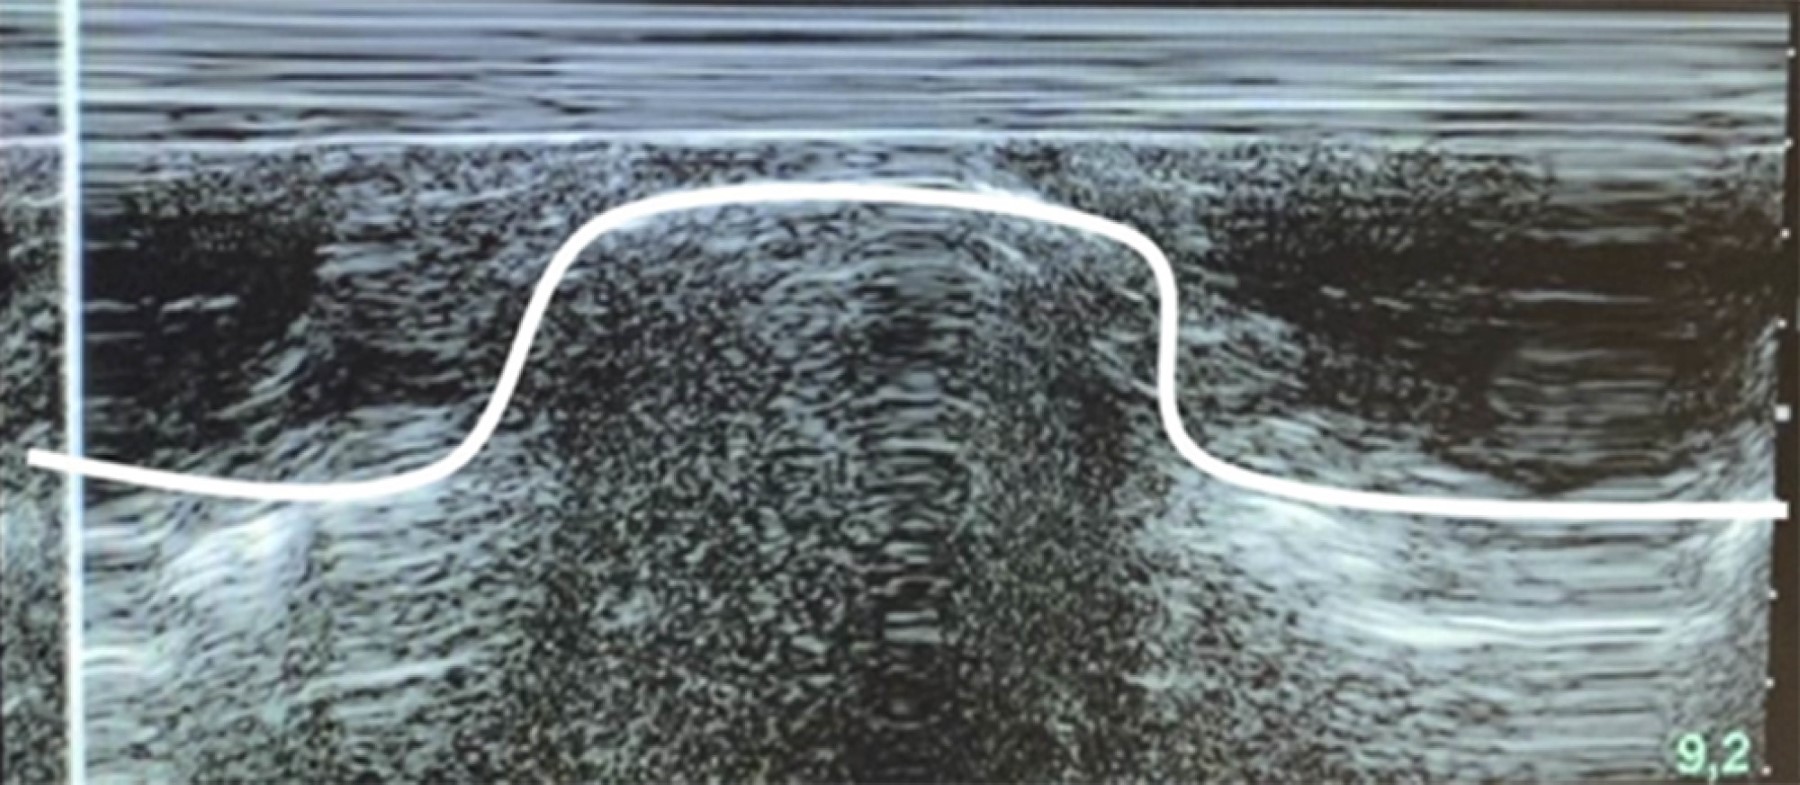

Ultrasound-guided bilateral brachial plexus block, supraclavicular and infraclavicular approach in upper limb surgery plus ultrasound-guided monitoring of diaphragmatic dynamics. A case report

Introduction: in anesthetic practice, bilateral brachial plexus block (BPB) is generally contraindicated due to the risks it entails, systemic toxicity from local anesthetics and bilateral phrenic nerve palsy. Since its indications are scarce, we present the case of a patient who was managed with bilateral regional anesthesia for both upper limbs at the same surgical time. Case presentation: 60-year-old male patient with diagnoses of Frikman III right distal radius fracture and Mayo III left olecranon fracture, scheduled for open reduction and internal fixation (ORIF) of the left olecranon and of the right distal radius, history of type 2 diabetes, systemic arterial hypertension and compensated chronic heart failure. Interventions: left supraclavicular and right infraclavicular BPB were performed as the only anesthetic procedure for bilateral upper limb surgery. Results: bilateral BPB was successful for bilateral upper limb surgery. The surgery was uneventful and without major complications. Conclusions: bilateral brachial plexus block is a safe technique when performed in different approaches, trying to minimize the risk of complications, providing better comfort in the immediate postoperative period of the patient by providing prolonged analgesia.

Figure 1